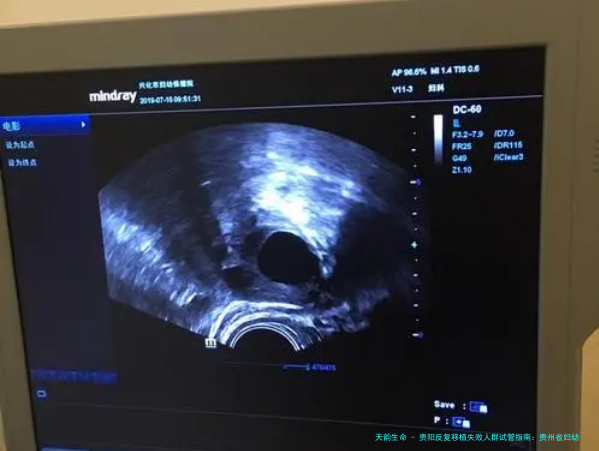

具体讲解:贵阳市妇幼保健院生殖医学中心的特色在于对移植失利原因的精细化排除检查。他们不仅留意胚胎,更着重对母体子宫内部环形境的透彻评价,如通过高清晰画质宫腔镜探测查寻内膜情况、评价血流等。对于免疫要素可能导致的失利,他们也有相应的检测和干涉预案。